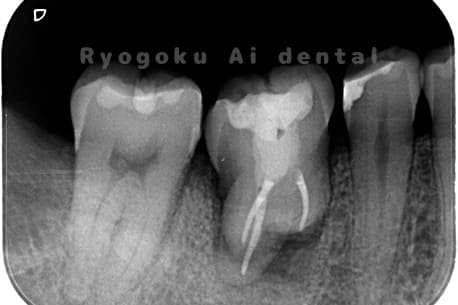

他院で右下の根の治療を行い、セラミックを被せる説明をされていたが、根の治療が終わらないため転院された患者さんです。隣の親知らずの抜歯の必要性と、根の治療を行なっている歯牙の予後が悪いため、移植治療を提案し、右下の親知らずの抜歯と同時に、右下の奥歯(7番)への移植治療を行いました。被せ物を行う必要もなく、順調に経過してます。